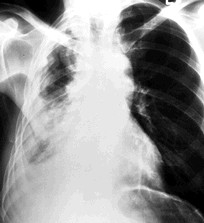

328) A 66 year old man is seen in your office for progressive shortness of breath on exertion for the past one year. He also reports dry cough. He denies any fever, hemoptysis or weight loss. He has no history of infections. He denies smoking. He has no other medical problems and has never been hospitalized. On examination, he is afebrile, blood pressure 120/80 mm Hg, RR 18/min and Pulse 82/min. There are no palpable chest-wall masses or lymphadenopathy. On auscultation, crackles are heard all over the lung fields, more pronounced at lung bases. Extremities show mild digital clubbing.

A chest x-ray is shown below:

Which of the following is expected to be seen with this disease?

A) Young age at onset

B) Rapid progression

C) High Resolution CT scans showing ill-defined cysts and pleural plaques

D) Poor or no response to steroids

E) Obstructive pattern on Pulmonary function tests